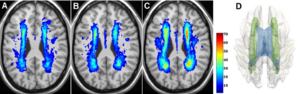

- 3.43 Functional Mapping of the Human Visual Cortex with Intravoxel Incoherent Motion MRI

- 3.45 A Gradient in Cortical Pathology in Multiple Sclerosis by in vivo Quantitative 7 T Imaging